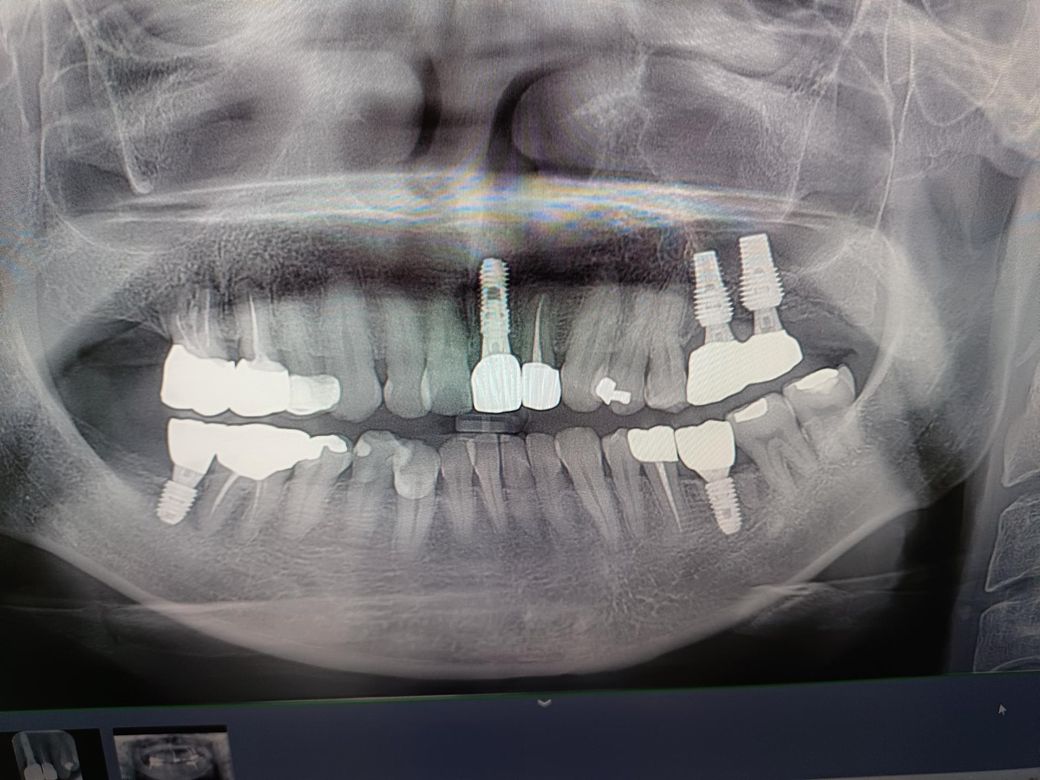

갑자기 신경치료 한 크라운 치아가 씹을때 약간 통증 있고 씹고나면 약간 욱신거리는데 8개월 전 에 찍은 사진보다 좀더 시커멓게 나오는데 충치인지 충치때문에 아픈건지 8개월만에 저렇게 변하는지 궁금합니다

저이빨이 3~4년전에 뒤쪽이빨 임플란트할때 혼자 힘을 많이받을때는 아픈적있었는데 임플란트하고 그뒤로는 몇년간 안아프다가 이제 조금씩 욱신거립니다 문의드립니다

파노라마 사진이 하나가 좌우반전이 되어 있네요

증상이 있으면 치근단 엑스레이 찍어보면 좋을 것 같습니다

충치가 잘 생길 조건이긴 하네요